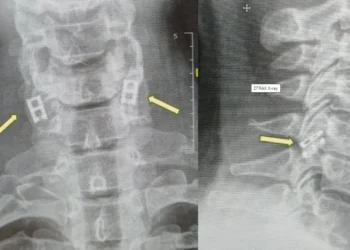

Μεταμόσχευση νωτιαίου μυελού με κύτταρα από τον ίδιο τον ασθενή για πρώτη φορά παγκοσμίως στο Ισραήλ. Επανάσταση στην αναγεννητική ιατρική!

Το Ισραήλ ετοιμάζεται να πραγματοποιήσει την πρώτη παγκοσμίως μεταμόσχευση ανθρώπινου νωτιαίου μυελού χρησιμοποιώντας τα ίδια τα κύτταρα του ασθενούς, μια...